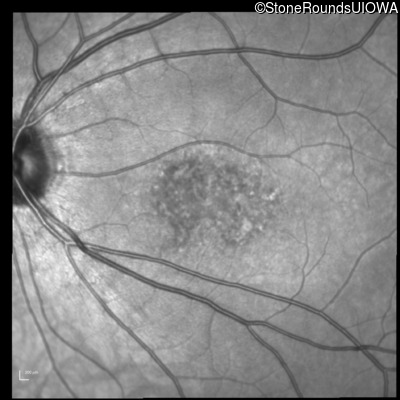

Infrared Fundus Photograph - Right - 20/32

Exemplar

Infrared Fundus Photograph - Left - 20/50